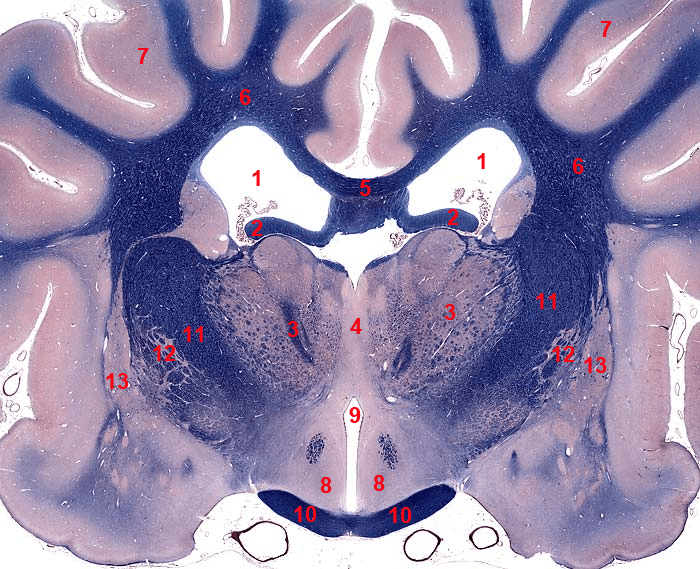

- Cosa indicano i numeri nella figura sottostante?

5. 1: ventricolo laterale; 2: gamba del fornice; 3: talamo; 4: adesione intertalamica; 5: corpo calloso; 6: sostanza bianca dell’emisfero cerebrale (corona radiata); 7: sostanza grigia dell’emisfero cerebrale (corteccia cerebrale); 8: ipotalamo; 9: III ventricolo; 10: chiasma ottico; 11: capsula interna; 12: pallido; 13: putamen